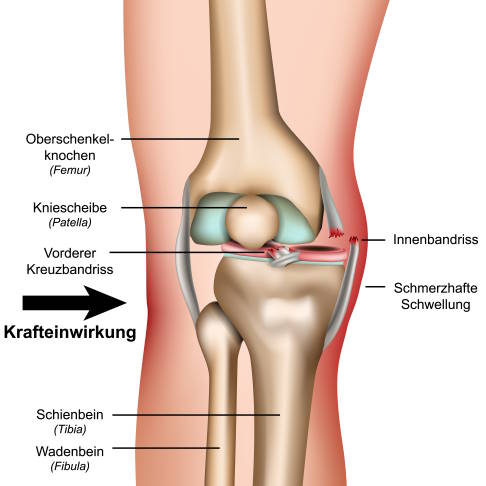

Eine weitere typische Ursache für einen vorderen Kreuzbandriss ist der Valguskollaps, also das Wegsacken des Knies nach innen. Dies passiert häufig, wenn der Betroffene in die Kniebeuge geht. Meist reißt dann nicht nur das vordere Kreuzband, sondern es kommt auch zum Innenbandriss und zur Verletzung des Innenmeniskus. Man spricht in diesem Fall von einer "Unhappy Triade" des Kniegelenks.

Zu 80 % resultieren aus einem Kreuzbandriss zusätzliche Verletzungen an anderen Strukturen im Knie:

- Riss des Innenmeniskus oder Außenmeniskus

- Knochen-Knorpelschäden

- sekundäre Kniearthrose als Folge der eingeschränkten Meniskusfunktion und fehlender stabilisierender Bänder

- Innenbandverletzung

- Außenbandverletzung

- Riss der Gelenkkapsel des Kniegelenks